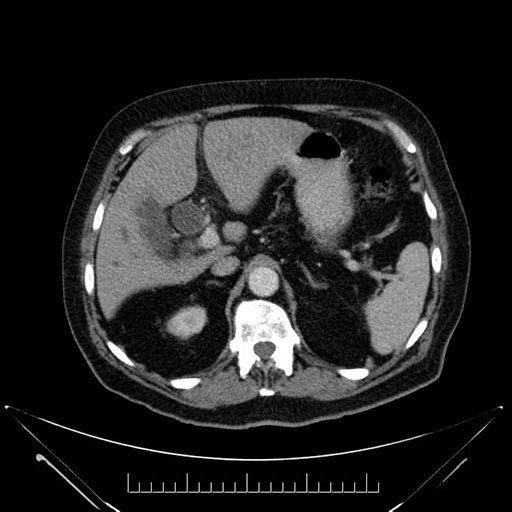

Imaging Analysis

Look through the patient's CT scan to identify any areas of concern for the necessary procedure.

Based on your CT findings, which issue(s) would give reason for "planned slowing down moment(s)" in this case?